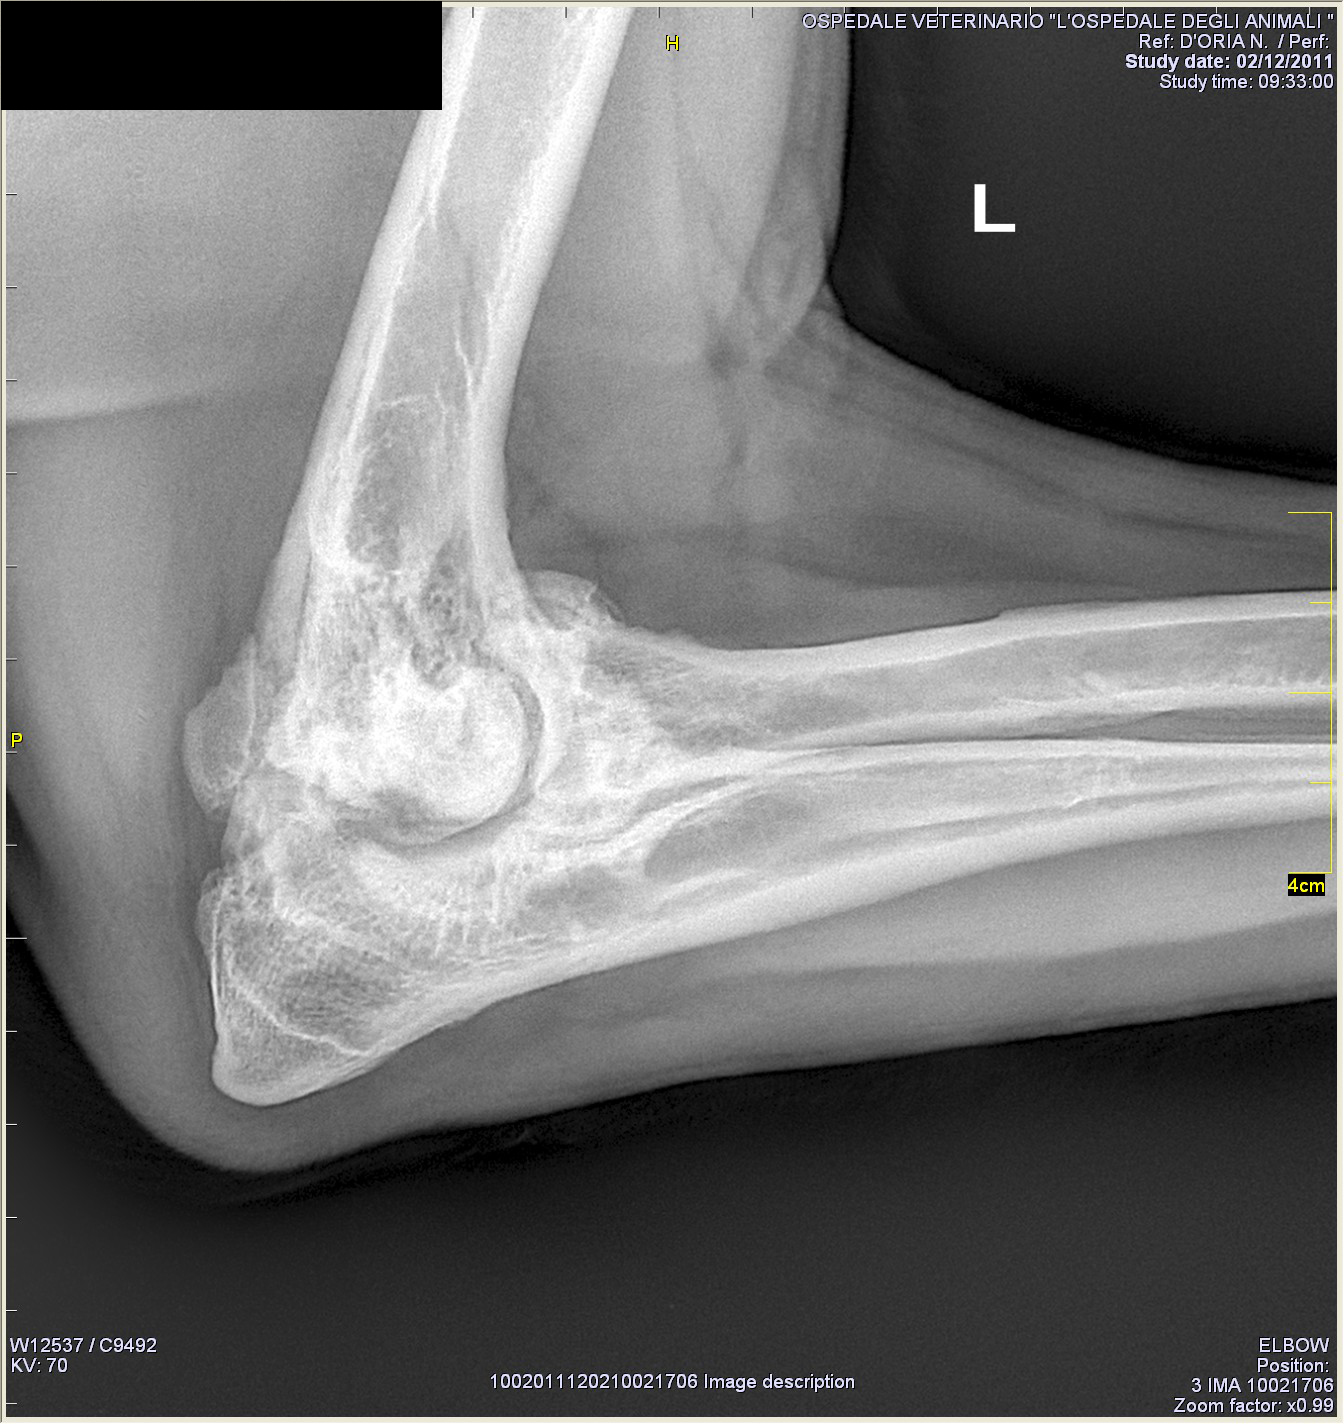

Artrosi del gomito di Pongo, cane Labrador Retriever |